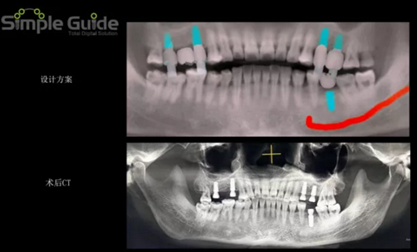

種植規(guī)劃與術(shù)后CBCT影像對(duì)比

繪制下頜神經(jīng)管

植體植入設(shè)計(jì)

設(shè)計(jì)植入5顆種植體